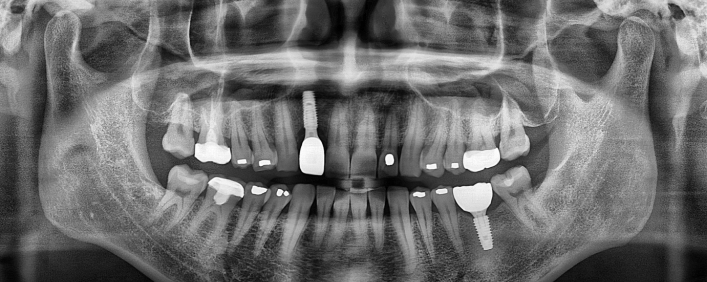

임플란트 치료사례

서울스마트치과는 결과로 증명합니다.

위 치료 사례는 서울스마트치과에서 직접 치료를 받고, 환자 본인의 동의를 얻어 게재된 사진으로 무단 인용, 도용, 재배포 시 민/형사상 책임을 질 수 있습니다.